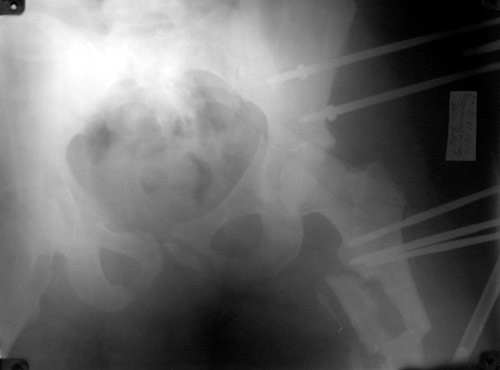

Re: перелом таза

То, что получилось в приложении. Стоит ли дальше тянуть головку винтами или низводить проксимальный отломок по оси?

По поводу ''Если речь о левом тазобедренном суставе, то это не вывих, а высокий

перелом вертлужной впадины, требующий оперативного лечения'' я не вполне понял.